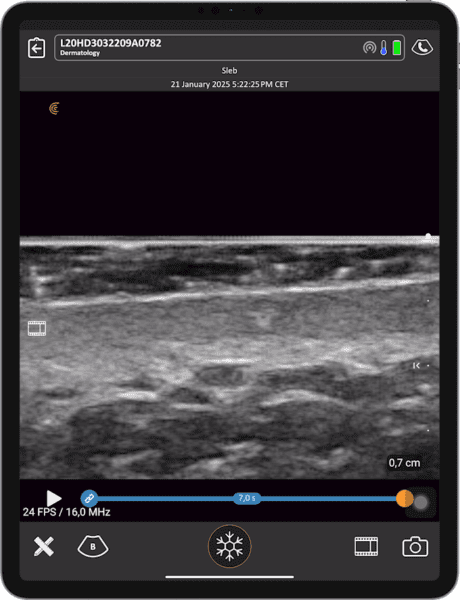

- Identificar la microanatomía de la piel y reconocer signos de envejecimiento e inflamación cutánea, como la banda subepidérmica de baja ecogenicidad (SLEB).

La ecografista Janaye Smith realizará un escaneo en vivo con el Clarius L20 HD3, nuestro escáner de ultraalta frecuencia diseñado para la estética facial, y demostrará cómo T-Mode™ facilita el aprendizaje de la ecografía.